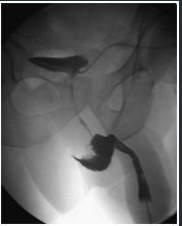

PRESENÇAÇ DE VIA BILIAR DILATA + CALCULO DENTRO DA VESICULA .

O EXAME DE IMAGEM É : CPRE ( NOTE A PRESENÇA DE CONSTRASTE )